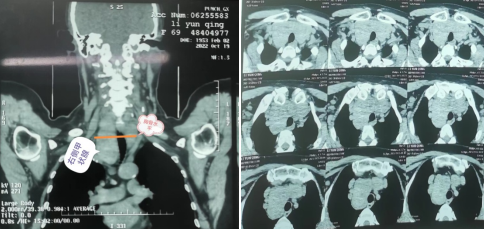

“巨大的瘤体上至甲状软骨上极、下至胸骨后主动脉弓水平,并且有三分之二的瘤体在胸骨后,气管严重受压变形”,代文杰教授为患者完善检查后发现李某甲状腺增大明显。李女士体型相对较胖,脖子较短,且合并甲亢,腺体血供丰富,手术风险巨大。

▲甲状腺CT影像显示气管受压,腺体下缘达到主动脉弓水平,2/3腺体位于胸骨后

由于肿瘤巨大,瘤体的三分之二居胸骨后,若术中进展不顺利,则需要劈开胸骨才可成功将腺体完整切除,并且患者脖子短、体型胖,使得经颈横切口切除巨大甲状腺肿瘤更为困难。除此以外患者高龄,伴有甲状腺功能亢进,不充分的术前准备、不轻柔的术中操作很容易引起术后甲状腺危象,一旦发生可在短时间内发展至昏迷、休克,甚至要了命。